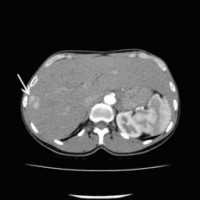

Computertomographische Darstellung eines hepatozellulären Karzinoms (Pfeil) (Bild 1 von 5) Vorwärts »